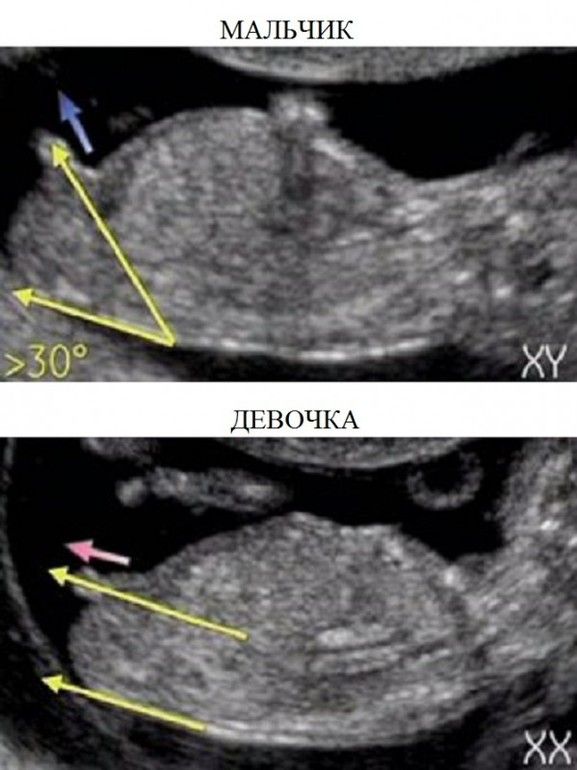

Если смотреть так, то девочка Изображение Изображение